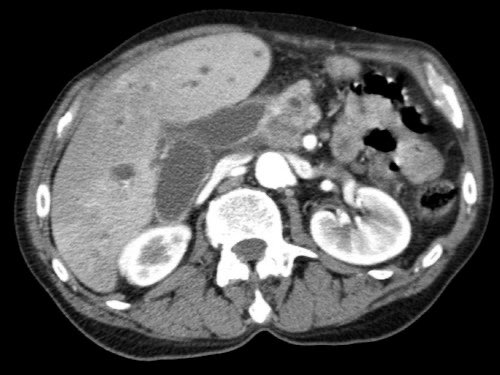

Tái tạo mặt phẳng coronal cho thấy:

- Bất thường bờ viền thành SMV được nhận thấy rõ hơn trên tái tạo coronal này (mũi tên).

- Khối u ở thân tụy (đầu mũi tên trắng).

- Huyết khối trong các nhánh bên của SMV (mũi tên xanh nhỏ).